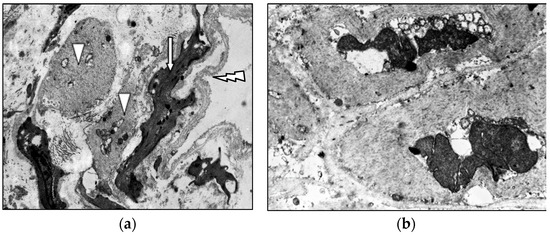

Age- and Varicose Disease-Associated Changes in the Muscular Components of the Great Saphenous Vein

by Khurshed A. Abduvosidov, Irina A. Chekmareva, Valeria G. Shestakova, Irina N. Shabanova, Alexander G. Alekseev, Edgar S. Kafarov, Alexander A. Palalov, Irina N. Yashina and Evgeny N. Galeysya

J. Clin. Med. 2025, 14(18), 6448; https://doi.org/10.3390/jcm14186448 - 12 Sep 2025

Varicose disease and other age-related vascular illnesses are extremely prevalent among the adult population. Despite this, research devoted to involutive changes in the veins of the lower extremities is rare and fragmented. Complex morphological evaluation of the wall of the vein related to [...] Read more.

Varicose disease and other age-related vascular illnesses are extremely prevalent among the adult population. Despite this, research devoted to involutive changes in the veins of the lower extremities is rare and fragmented. Complex morphological evaluation of the wall of the vein related to age and varicose disease can add valuable data to fundamental geriatric and vascular medicine. Objectives: The study was designed to determine the age-related changes in the muscular component of the great saphenous vein and changes associated with varicose disease. Materials and Methods: A morphological study of a specimen of the great saphenous vein was conducted on 55 deceased individuals and 80 patients with varicose disease. Four age subgroups were identified: young, middle-aged, elderly, and senile. A total of 135 fragments of the great saphenous vein were evaluated. Histological, morphometric, and electron microscopic studies were performed. A quantitative analysis of the volumetric fraction of muscular components was calculated using the Shapiro–Wilk test, Kruskal–Wallis (ANOVA) and Mann–Whitney methods with Bonferroni correction. Results: Our study showed that the amount of connective tissue elements between bundles of smooth muscle cells increased with age. In patients with varicose disease, we observed an appearance of connective tissue fibers among smooth muscle cells, more pronounced with the disease progression. The structure of smooth muscle cell changes. Thus, we observed hypertrophy and phenotypic heterogeneity of cells with subsequent destruction of communicative contacts. The values of subintimal longitudinally arranged smooth muscle cells reached their maximum in middle age in both normal and varicose veins, while significant decrease occurred in elderly and senile patients. Quantitative indicators of circularly arranged smooth muscle cells of the middle layer did not change with age but significantly decreased in varicose disease. Age-related changes are characterized by an increase in the proportion of smooth muscle cells in the outer layer. In varicose veins, in young and middle-aged patients, the content of bundles of longitudinally arranged smooth muscle cells in the outer layer was higher compared to the age norm, with a significant decrease in senile age. Conclusions: The age norm of the muscular component of the great saphenous vein wall is characterized by an increase in the volumetric fraction of subintimal longitudinally arranged smooth muscle cells in middle age, the volumetric fraction of circularly arranged smooth muscle cells of the middle layer remains unchanged, and the volumetric fraction of bundles of longitudinally arranged myocytes of the outer layer increases. With age in varicose disease, sclerotic changes progress in the structure of the great saphenous vein at the tissue, cellular, and intracellular levels, leading to a decrease in the volumetric fraction of all muscular components of the great saphenous vein structure. Full article